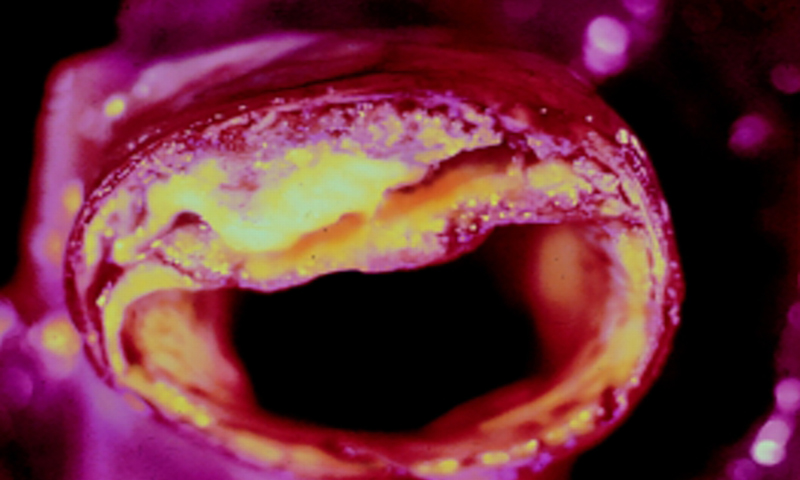

Artères bouchées: 3 ingrédients naturels pour les nettoyer

Artères bouchées

Si vos artères sont bouchées, sachez qu’il existe trois ingrédients efficaces qui peuvent améliorer, voire déboucher, les artères bouchées et éliminer la graisse du sang.

Les artères transportent les nutriments et l’oxygène vers le cœur et les autres organes du corps. Pour préserver votre santé, les artères doivent rester propres en permanence. C’est pour cette raison que l’alimentation est extrêmement importante pour vous et vos artères. Les produits transformés, les aliments gras, les toxines et les produits chimiques peuvent avoir des effets graves sur la santé cardiovasculaire et avec le temps ils peuvent entraîner des problèmes cardiaques graves.